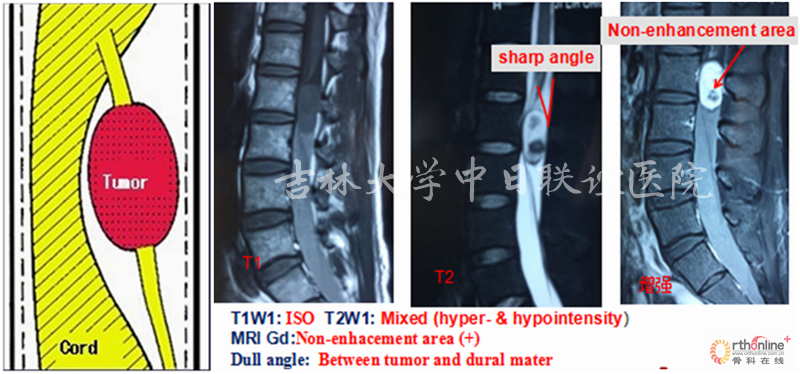

MRI:T1W1:相对脊髓呈等信号;T2W1:相对脊髓呈略高信号,瘤体与硬膜呈锐角,脑脊液在瘤体上缘增宽呈“杯口征”(瘤体位于硬膜下);MRI Gd:肿瘤边缘明显强化,瘤体中央伴有不均匀性增强。肿瘤与脊髓之间呈锐角,形成“肩胛征”,脊髓呈鸟嘴样改变(髓外)。

X线平片和CT检查均需要依据钙化或肿瘤引起的明显骨质改变而检出病灶,阳性率较低,但是有助于了解脊柱的稳定程度、对手术方案的制定提供帮助;脊髓造影为有创性检查,通过肿瘤与造影剂的作用(如表现为充盈缺损等)对肿瘤的定位诊断有一定的帮助,但是对于肿瘤定性存在困难。MRI对椎管内软组织分辨率高并且能够避免骨骼的伪影,根据不同肿瘤相对特征性的MRI表现可以获得较为准确可靠的定位及定性诊断,有利于术前制定合理的手术方案。

神经鞘瘤(Neurinoma)

我们回顾性分析了我院108例(111个病灶)硬膜下髓外肿瘤病例特点;神经鞘瘤69(70病灶),脊膜瘤31(31病灶),神经纤维瘤3(5病灶),畸胎瘤4(4病灶),转移性肿瘤1(1病灶)。不同肿瘤的MRI表现具有一定的特异性: